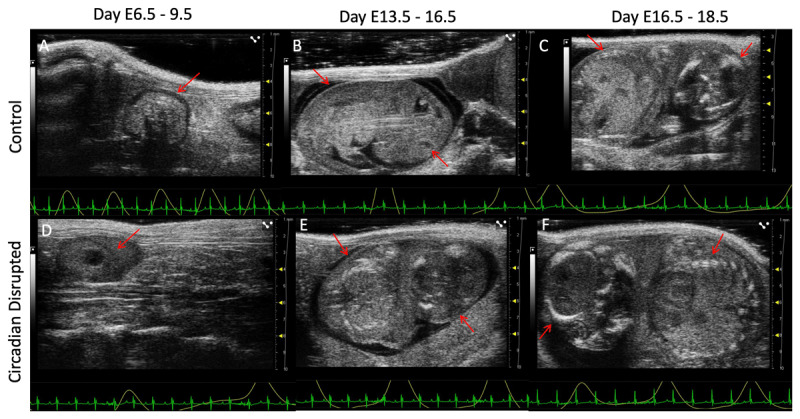

健康和疾病理论的发育起源表明,生命早期,特别是产前生活期间的环境暴露可以极大地影响生命后期的健康状况。不规律的明暗周期,如轮班工作期间的经历,导致昼夜节律的反复中断,这对生理和行为周期产生负面影响。我们的研究目的是在暴露于昼夜节律中断时,使用高频超声评估发育中的小鼠胚胎和胎儿的参数。怀孕的雌性小鼠在怀孕期间接受提前7小时的昼夜节律中断方案,或保持正常的12/12光暗周期。妊娠14.5 ~ 18.5时,胎盘长度(p = 0.00016)、胎盘厚度(p = 0.0332)、胃直径(p = 0.0186)差异均有统计学意义。这些发现表明,模仿轮班工作的怀孕水坝的昼夜节律中断改变了子宫内特定器官的胚胎和胎儿发育。

The developmental origins of health and disease theory suggests that environmental exposures during early life, particularly during prenatal life, can greatly influence health status later in life. Irregular light-dark cycles, such as those experienced during shift work, result in the repeated disruption of circadian rhythms, which negatively impacts physiological and behavioral cycles. The purpose of our study was to assess parameters in the developing mouse embryo and fetus using high frequency ultrasound when exposed to circadian disruption. Pregnant female mice were subjected to a seven-hour advanced circadian disrupted protocol or remained on a normal 12/12 light-dark cycle throughout pregnancy. Significant differences were observed in placental length (p = 0.00016), placental thickness (p = 0.0332), and stomach diameter (p = 0.0186) at E14.5-18.5. These findings suggest that circadian disruption in pregnant dams, mimicking shift work, alters embryonic and fetal development in specific organs in utero.